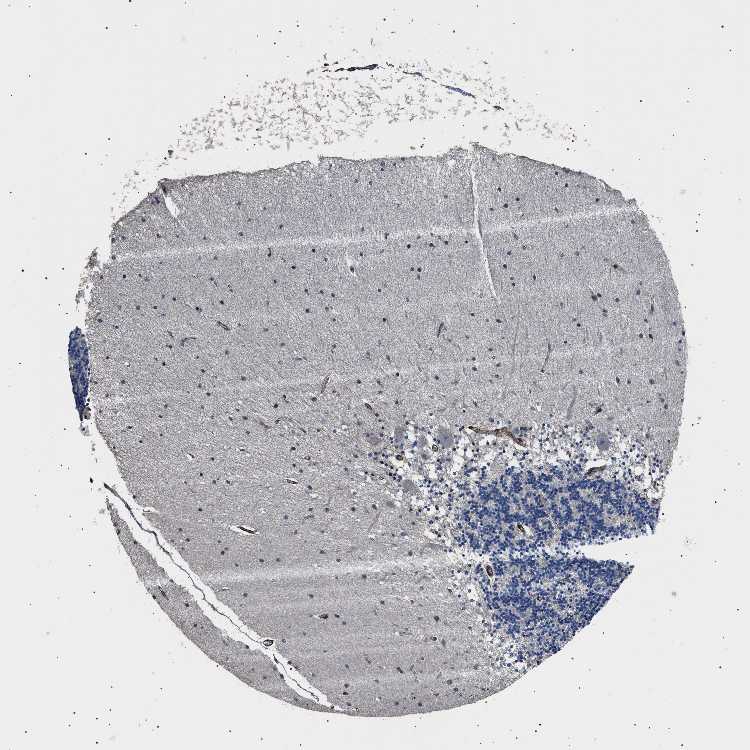

CEREBELLUM - Antibody stainingi

Antibody staining in the annotated cell types in the current human tissue is reported as not detected, low, medium, or high, based on conventional immunohistochemistry profiling in selected tissues. This score is based on the combination of the staining intensity and fraction of stained cells.

Each image is clickable and will lead to virtual microscopy that enables deeper exploration of all samples and also displays staining intensity scores, fraction scores and subcellular localization as well as patient and tissue information for each sample.

Antibody HPA020386

Purkinje cells Not detected

Cells in granular layer Not detected

Cells in molecular layer Not detected